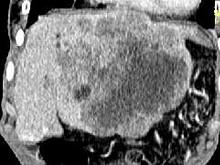

问题 女,73岁,中上腹痛1月余,患者黄疸、消瘦,CT检查如下图,最可能的诊断是()

选项 A.肝脓肿 B.巨块型肝癌 C.肝血管瘤 D.肝淋巴管瘤 E.肝胆管细胞癌

答案 B